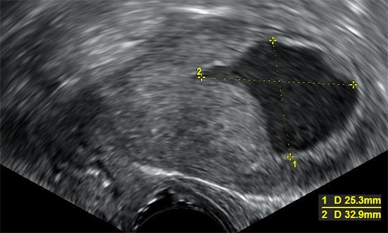

Transvaginal ultrasonography showing uterine fluid accumulation. Biopsy showed endometrioid adenocarcinoma.